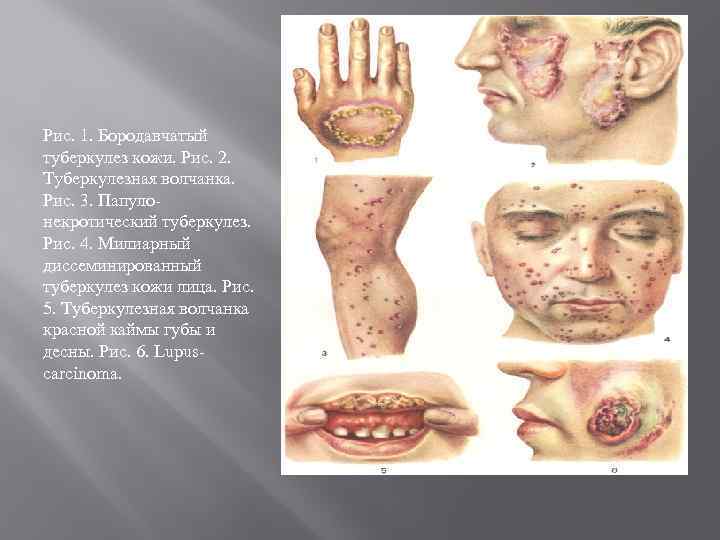

Туберкулез кожи Первичный туберкулез кожи развивается при попадании микобактерии туберкулеза на поврежденную кожу извне у лиц, ранее не инфицированных туберкулезом. На месте внедрения возбудителя инфекции, чаще на губах, образуется бугорок (первичный аффект), который впоследствии изъязвляется. В патологический процесс вовлекаются регионарные лимфатические узлы. Через несколько дней (недель) очаг поражения отграничивается и обызвествляется. Эта форма туберкулеза кожи встречается чрезвычайно редко. В большинстве случаев туберкулез кожи – вторичное проявление туберкулезной инфекции (вторичный туберкулез кожи). Он развивается чаще вследствие заноса в кожу возбудителей туберкулеза из очагов в других органах гематогенным и (или) лимфогенным путем, а также по соприкосновению

Туберкулез кожи Первичный туберкулез кожи развивается при попадании микобактерии туберкулеза на поврежденную кожу извне у лиц, ранее не инфицированных туберкулезом. На месте внедрения возбудителя инфекции, чаще на губах, образуется бугорок (первичный аффект), который впоследствии изъязвляется. В патологический процесс вовлекаются регионарные лимфатические узлы. Через несколько дней (недель) очаг поражения отграничивается и обызвествляется. Эта форма туберкулеза кожи встречается чрезвычайно редко. В большинстве случаев туберкулез кожи – вторичное проявление туберкулезной инфекции (вторичный туберкулез кожи). Он развивается чаще вследствие заноса в кожу возбудителей туберкулеза из очагов в других органах гематогенным и (или) лимфогенным путем, а также по соприкосновению

Туберкулезная волчанка, или волчаночный туберкулез кожи, развивается при заносе микобактерии туберкулеза в кожу гематогенным и лимфогенным путем. На коже лица (нос, губы, щеки, ушные раковины и др. ), на слизистой оболочке носа и рта, реже на коже туловища и конечностях появляются мягкие красновато-оранжевые бугорки диаметром от 0, 2 до 0, 8 см. Сливаясь, они образуют более крупные очаги поражения Колликвативный туберкулез кожи, или скрофулодерма, развивается вследствие попадания в кожу микобактерий туберкулеза преимущественно лимфогенным путем и по соприкосновению (из лимфатических узлов, суставов). Характеризуется появлением в дерме (собственно коже) и подкожной основе шаровидного узла диаметром 0, 5– 3 см. Чаще узел располагается в области крупных лимфатических узлов (поднижнечелюстных, шейных, подмышечных, паховых) и по краю грудины. Вначале узел небольшой, подвижный. Постепенно он увеличивается и спаивается с окружающими тканями. Кожа над ним истончается, приобретает синюшно-красный цвет. Затем узел некротизируется и прорывается в нескольких местах наружу с выделением жидкого гноя и крошковатых масс. После заживления остаются характерные неровные рубцы с «сосочками» и «мостиками» , позволяющие безошибочно ретроспективно установить перенесенный колликвативный туберкулез кожи.

Туберкулезная волчанка, или волчаночный туберкулез кожи, развивается при заносе микобактерии туберкулеза в кожу гематогенным и лимфогенным путем. На коже лица (нос, губы, щеки, ушные раковины и др. ), на слизистой оболочке носа и рта, реже на коже туловища и конечностях появляются мягкие красновато-оранжевые бугорки диаметром от 0, 2 до 0, 8 см. Сливаясь, они образуют более крупные очаги поражения Колликвативный туберкулез кожи, или скрофулодерма, развивается вследствие попадания в кожу микобактерий туберкулеза преимущественно лимфогенным путем и по соприкосновению (из лимфатических узлов, суставов). Характеризуется появлением в дерме (собственно коже) и подкожной основе шаровидного узла диаметром 0, 5– 3 см. Чаще узел располагается в области крупных лимфатических узлов (поднижнечелюстных, шейных, подмышечных, паховых) и по краю грудины. Вначале узел небольшой, подвижный. Постепенно он увеличивается и спаивается с окружающими тканями. Кожа над ним истончается, приобретает синюшно-красный цвет. Затем узел некротизируется и прорывается в нескольких местах наружу с выделением жидкого гноя и крошковатых масс. После заживления остаются характерные неровные рубцы с «сосочками» и «мостиками» , позволяющие безошибочно ретроспективно установить перенесенный колликвативный туберкулез кожи.

Индуративный туберкулез кожи (индуративная эритема Базена) развивается при гематогенном и лимфогенном инфицировании кожи микобактериями туберкулеза. Болеют в основном молодые женщины. Заболевание обостряется и рецидивирует чаще ранней весной или позднем осенью. В дерме и подкожной основе, преимущественно в области голеней появляются малоболезненные продолговатые инфильтраты или узлы диаметром до 3 см, между которыми нередко образуются шнурообразные перетяжки. Кожа над очагами поражения приобретает синюшно-багровый цвет Инфильтраты и узлы разрешаются «сухим путем» либо частично распадаются и изъязвляются. Язвы неглубокие, с мягкими нависающими краями и скудным серозно-гнойно-кровянистым отделяемым При заживлении язв образуются рубцы. Бородавчатый туберкулез кожи в подавляющем большинстве случаев является результатом профессионального экзогенного заражения Инфицирование происходит от больных туберкулезом людей и животных (или трупов), а также при соприкосновении с предметами. загрязненными патологическим материалом, содержащим микобактерии туберкулеза. Поражаются преимущественно пальцы рук в области макро- и микротравм. Первичным морфологическим элементом является бугорок диаметром 0, 5– 1, 5 см, сформировавшийся бугорок имеет 4 зоны: в центре находится язва, к ней прилежат бородавчатые разрастания со щелями и трещинами, из которых при надавливании выделяется гной, затем располагаются воспалительный валик и по периферии – венчик застойной гиперемии. Могут поражаться регионарные лимфатические узлы, но далее процесс обычно не распространяется.

Индуративный туберкулез кожи (индуративная эритема Базена) развивается при гематогенном и лимфогенном инфицировании кожи микобактериями туберкулеза. Болеют в основном молодые женщины. Заболевание обостряется и рецидивирует чаще ранней весной или позднем осенью. В дерме и подкожной основе, преимущественно в области голеней появляются малоболезненные продолговатые инфильтраты или узлы диаметром до 3 см, между которыми нередко образуются шнурообразные перетяжки. Кожа над очагами поражения приобретает синюшно-багровый цвет Инфильтраты и узлы разрешаются «сухим путем» либо частично распадаются и изъязвляются. Язвы неглубокие, с мягкими нависающими краями и скудным серозно-гнойно-кровянистым отделяемым При заживлении язв образуются рубцы. Бородавчатый туберкулез кожи в подавляющем большинстве случаев является результатом профессионального экзогенного заражения Инфицирование происходит от больных туберкулезом людей и животных (или трупов), а также при соприкосновении с предметами. загрязненными патологическим материалом, содержащим микобактерии туберкулеза. Поражаются преимущественно пальцы рук в области макро- и микротравм. Первичным морфологическим элементом является бугорок диаметром 0, 5– 1, 5 см, сформировавшийся бугорок имеет 4 зоны: в центре находится язва, к ней прилежат бородавчатые разрастания со щелями и трещинами, из которых при надавливании выделяется гной, затем располагаются воспалительный валик и по периферии – венчик застойной гиперемии. Могут поражаться регионарные лимфатические узлы, но далее процесс обычно не распространяется.

Папулонекротический туберкулез кожи развивается преимущественно в детском, юношеском и молодом возрасте при гематогенном заносе микобактерий туберкулеза в кожу. Поражается главным образом кожа разгибательных поверхностей конечностей, ягодиц, лица, в т. ч. ушных раковин, где появляются множественные высыпания. Первичным морфологическим элементом сыпи является шаровидный цианотично-бурый бугорок диаметром 0, 2– 0, 3 см, который по виду напоминает папулу. Бугорок распадается, но некротические массы не отторгаются, а засыхают в плотно прикрепленную пробкообразную корку, если ее удалить (что не рекомендуется), то под ней обнаруживается язва. На месте заживших бугорков остаются округлые вдавленные бесцветные «штампованные» рубчики. Обнаружение подобных рубчиков на соответствующих участках кожи достоверно свидетельствует о перенесенном заболевании. Лихеноидный туберкулез кожи (лишай золотушных) возникает чаще в результате гематогенной диссеминации микобактерии туберкулеза и всегда сочетается с другими туберкулезными поражениями кожи, например с туберкулезной волчанкой, колликвативным туберкулезом. Характеризуется образованием множественных конических желтовато-розовых бугорков диаметром 0, 1– 0, 2 см, покрытых плотно прикрепленными чешуйками. Бугорки располагаются преимущественно на коже туловища скоплениями по несколько десятков, но не сливаются. При пальпации отмечается шероховатость кожи – «симптом терки» . Субъективные ощущения отсутствуют.

Папулонекротический туберкулез кожи развивается преимущественно в детском, юношеском и молодом возрасте при гематогенном заносе микобактерий туберкулеза в кожу. Поражается главным образом кожа разгибательных поверхностей конечностей, ягодиц, лица, в т. ч. ушных раковин, где появляются множественные высыпания. Первичным морфологическим элементом сыпи является шаровидный цианотично-бурый бугорок диаметром 0, 2– 0, 3 см, который по виду напоминает папулу. Бугорок распадается, но некротические массы не отторгаются, а засыхают в плотно прикрепленную пробкообразную корку, если ее удалить (что не рекомендуется), то под ней обнаруживается язва. На месте заживших бугорков остаются округлые вдавленные бесцветные «штампованные» рубчики. Обнаружение подобных рубчиков на соответствующих участках кожи достоверно свидетельствует о перенесенном заболевании. Лихеноидный туберкулез кожи (лишай золотушных) возникает чаще в результате гематогенной диссеминации микобактерии туберкулеза и всегда сочетается с другими туберкулезными поражениями кожи, например с туберкулезной волчанкой, колликвативным туберкулезом. Характеризуется образованием множественных конических желтовато-розовых бугорков диаметром 0, 1– 0, 2 см, покрытых плотно прикрепленными чешуйками. Бугорки располагаются преимущественно на коже туловища скоплениями по несколько десятков, но не сливаются. При пальпации отмечается шероховатость кожи – «симптом терки» . Субъективные ощущения отсутствуют.

Язвенный туберкулез кожи и слизистых оболочек развивается при тяжелом течении туберкулеза гортани, легких, почек, кишечника и других органов. Микобактерии туберкулеза попадают на кожу и слизистые оболочки с мокротой, мочой, калом и другими выделениями, поэтому очаги поражения располагаются в области естественных отверстий: вокруг рта, ноздрей, половой щели, заднего прохода, наружного отверстия мочеиспускательного канала. Первичным морфологическим элементом является шаровидный бугорок диаметром 0, 1 – 0, 2 см. Бугорки множественные тесно соприкасаются между собой и быстро изъязвляются. Язвы резко болезненны, имеют причудливые очертания (полициклические, мелкофестончатые) с воспалительным венчиком по периферии, желтоватое дно, покрытое мелкими узелками – «зернами Трела» (представляющими собой казеозно-перерожденные бугорки). В гнойном отделяемом язв содержится большое количество микобактерий туберкулеза. Болезнь протекает на фоне анергии, поэтому туберкулиновые пробы отрицательны.

Язвенный туберкулез кожи и слизистых оболочек развивается при тяжелом течении туберкулеза гортани, легких, почек, кишечника и других органов. Микобактерии туберкулеза попадают на кожу и слизистые оболочки с мокротой, мочой, калом и другими выделениями, поэтому очаги поражения располагаются в области естественных отверстий: вокруг рта, ноздрей, половой щели, заднего прохода, наружного отверстия мочеиспускательного канала. Первичным морфологическим элементом является шаровидный бугорок диаметром 0, 1 – 0, 2 см. Бугорки множественные тесно соприкасаются между собой и быстро изъязвляются. Язвы резко болезненны, имеют причудливые очертания (полициклические, мелкофестончатые) с воспалительным венчиком по периферии, желтоватое дно, покрытое мелкими узелками – «зернами Трела» (представляющими собой казеозно-перерожденные бугорки). В гнойном отделяемом язв содержится большое количество микобактерий туберкулеза. Болезнь протекает на фоне анергии, поэтому туберкулиновые пробы отрицательны.